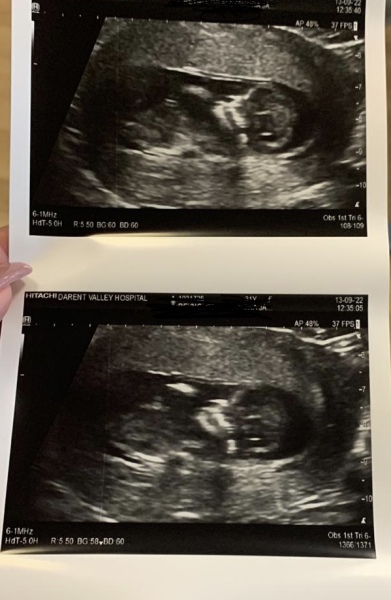

Hi everyone! Hope everyone’s doing ok. Currently on our delayed honeymoon/baby moon and thought I’d do a bit of baby shopping online, but wondered if you all had any thoughts of baby is a boy or girl?! We’re not finding out but I’m secretly so desperate to know and it’s making shopping a lot harder 😂 this was my 20 week scan, we think girl but interested to see what others think

@AGirlsNameIsAryaStark I don't think there's a way to tell from 20 week scans other than looking at their bits - do you have a 12 week scan you could post? I do love a guess at skull/nub theory

@TeddyBeans ah I thought so. I’ve done so much research I’m pretty sure when they measured the legs I saw the 3 lines everyone talks about for a girl but it was so quick! Our 12 week scans weren’t great photos, baby isn’t the most cooperative!

@AGirlsNameIsAryaStark from the 12 week skull I'd be inclined to say a girl. If you saw 3 lines I think you've got a pretty safe bet. Boys are incredibly obvious at 20 weeks, you'd be hard pressed to miss it 😁

Yeah 3 lines on my scan and it’s a girl